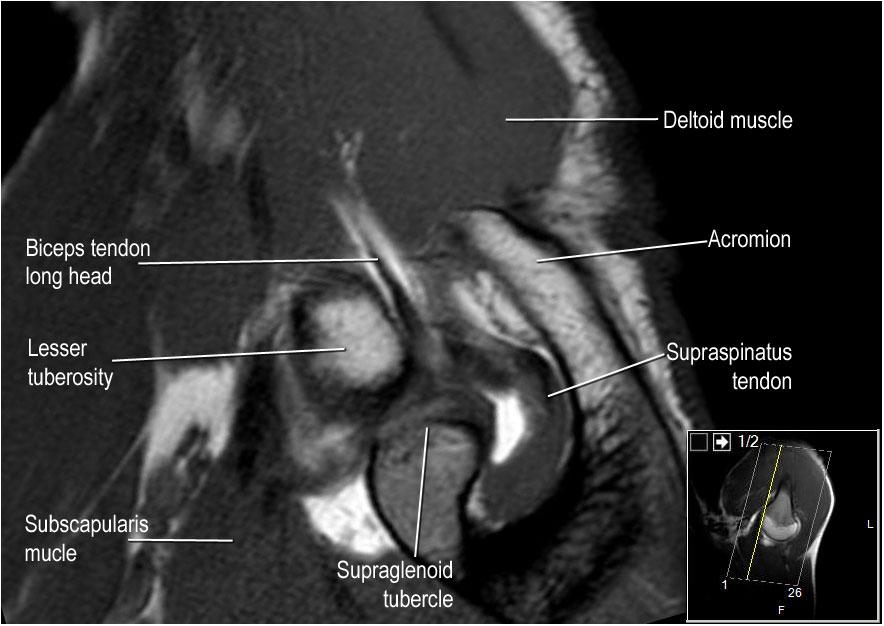

Hình ảnh mặt trước

Gân cơ dưới vai bám vào cả mấu động nhỏ lẫn mấu động lớn, đồng thời nâng đỡ đầu dài của gân cơ nhị đầu trong rãnh gian mấu động.

Trật khớp của đầu dài gân cơ nhị đầu chắc chắn sẽ dẫn đến rách một phần gân cơ dưới vai.

Chóp xoay được cấu thành từ các gân của cơ dưới vai, cơ trên gai, cơ dưới gai và cơ tròn bé.